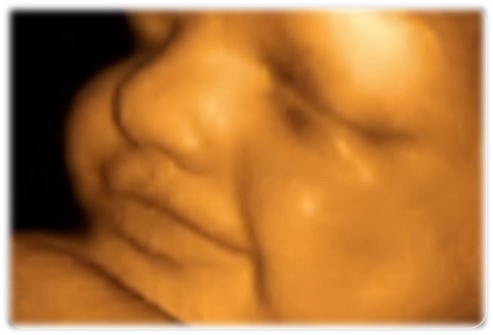

الإسبوع العشرين .. يصل وزن الجنين إلى 252 غرام وطوله إلى 15 سنتيمتر. يمكنه الآن وضع إبهمه في فمه ، مد أطرافه والتثاوب. تظهر في هذه المرحله التعابير على وجهه كلإبتسامه. وستشعر الأم بحركاته داخل بطنها

تأخذ صوره بالأشعه الفوق سمعيه (ultra-sound) للجنين عادة في الإسبوع العشرون. في هذا الفحص يتأكد الطبيب بأن الحبل السري مربوط بالجنين والأم بشكل سليم. يتمكن الطبيب أيضاً من رؤية حركة اليدين والقدمين وكذلك رؤية دقات القلب. في هذه المرحله من الممكن التعرف على جنس الجنين